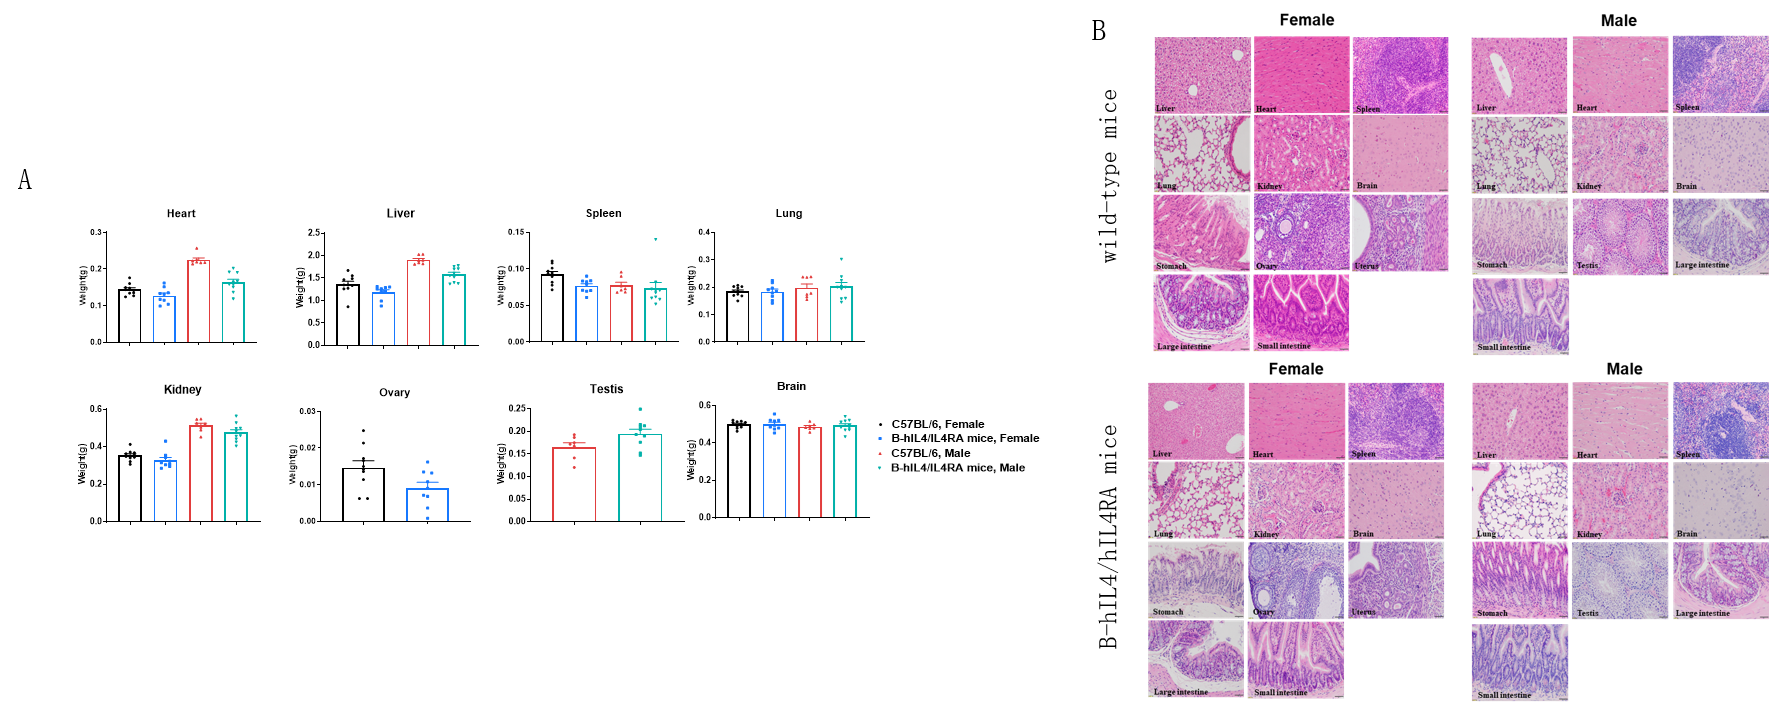

Macroscopic anatomical data of wild-type mice and B-hIL4/hIL4RA mice. 8-week-old wild-type C57BL/6 mice and B-hIL4/hIL4RA mice (10 males and 10 females) were monitored for 32 weeks to assess overall health of the animals. (A) Absolute body weight and percent weight gain of wild-type mice and B-hIL4/hIL4RA mice over time. (A) Organ weight of wild-type mice and B-hIL4/hIL4RA mice.(B) Organ histology (H&E) of wild-type mice and B-hIL4/hIL4RA mice. The morphology of organs and pathological examination of B-hIL4/hIL4RA mice revealed no abnormalities compared to wild-type controls.